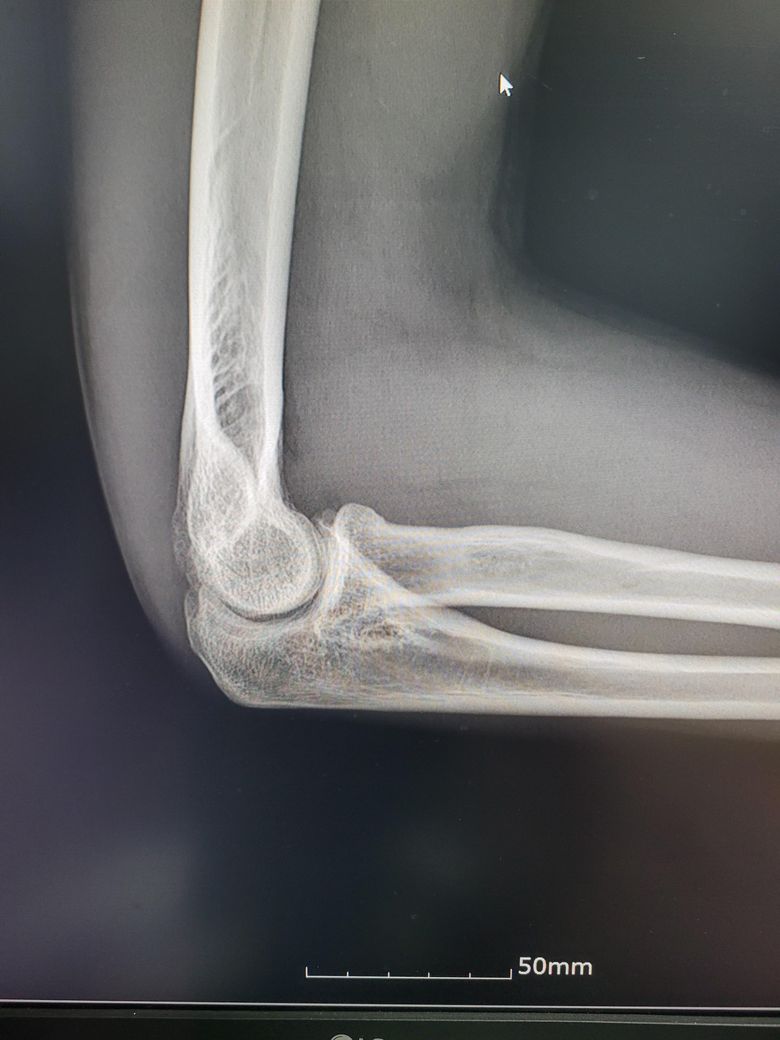

팔이 아파서 여러병원 찾아다니느라 엑스레이 사진도 복사해왔는데 1,2년 전에 비해서 팔꿈치에 동그란 게 생겼더라구여 이게 뭔지 모르겠습니다

과거에 활액막연골종으로 같은 부위를 수술받은 적이 있습니다

• 4번 째 사진

정확한 진단을 위해 엑스레이 외에도 MRI, CT촬영과 같은 추가 검사가 필요 할 수 있습니다 전문의와 상담하는 것이 좋을 것 같습니다.

질문자님께서 질문주신 활액막연골종증(윤활막연골종) 인지 확인이 필요하시다면 MRI 촬영 후 의사선생님께 여쭈어 보시는 것이 낫겠습니다.

활액막연골종증은 수술 후 재발률이 낮다고 알려져 있으니 이전에 수술하셨던 병원의 주치의 선생님께 진료 예약을 잡으시고 여쭈어보시는 것이 좋을 것 같습니다.

구조상 큰 변화는 없어 보입니다. 그러나, 정확한 소견은 전문의의 판독결과를 들어보시는 것이 가장정확하고, 연부조직의 염증같은 경우에는 엑스레이 보다는 초음파나 MRI와 같은 검사방법이 정확한 검사를 시행할 수 있겠습니다. 주치의와 상의 후에 판독결과나 추가적인 검사등에 대한 상담을 받아보시고, 필요시에는 검사를 받으시는 것이 좋겠습니다.